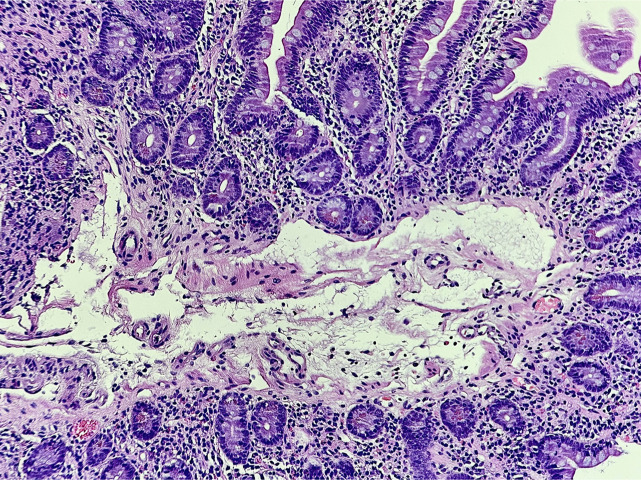

原发性肠淋巴血管扩张是一种罕见的疾病,其特征是小肠淋巴血管扩张,导致蛋白质,特别是白蛋白流失到胃肠道,从而导致蛋白质丢失性肠病。我们报告一个66岁的非裔美国人的情况下,谁提出了隐性腹痛,慢性腹泻,低白蛋白血症,白细胞减少和贫血。通过多模式诊断方法,包括视频胶囊内镜和小肠内镜活检,证实了水肿亚型原发性肠淋巴管扩张合并蛋白质丢失性肠病的难以诊断。治疗的重点是优化患者的营养状况。

Primary intestinal lymphangiectasia is a rare disorder characterized by the dilation of lymphatic vessels in the small intestine, resulting in the loss of proteins, particularly albumin, into the gastrointestinal tract which leads to a protein-losing enteropathy. We report the case of a 66-year-old African American man who presented with insidious abdominal pain, chronic diarrhea, hypoalbuminemia, leukopenia, and anemia. An elusive diagnosis of edematous subtype primary intestinal lymphangiectasia with protein-losing enteropathy was confirmed through a multimodal diagnostic approach, including video capsule endoscopy and small bowel endoscopy with biopsies. Treatment was focused on optimizing the patient's nutritional status.